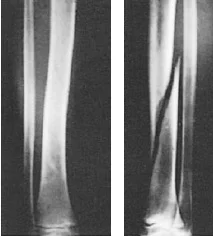

Classification by Fracture Line

- According to fracture line:

Complete (usual)

- Cortex fractured on both sides

Incomplete (in children)

- Green stick / Torus, Buckle /Deformation

Classification by Fracture Pattern

- According to fracture pattern:

- Simple

- Wedge comminuted

- Complex comminuted

- Multi-fragmented

Fracture Pattern and Mechanism of Force

- Fracture pattern suggests mechanism of force

- Spiral: (twisting)

- Short oblique: (compression)

- Wedge: (compression + bending)

- Transverse: (angulation) (avulsion)